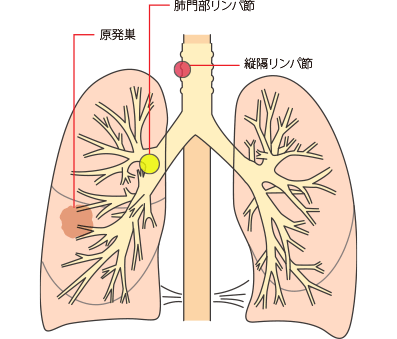

限局型小細胞肺がんの病変の範囲

リンパ節への転移とステージ・症状

肺がんでは、肺門(肺の入り口周辺)リンパ節、肺内(肺の中)リンパ節、縦隔(左右の肺に挟まれた空間)リンパ節という3つのグループに分かれます。

所属リンパ節への転移の段階はN因子(NX、N0、N1、N2、N3)で表され、病期(ステージ)を決める要素の一つです。数字が大きくなるほど、転移の範囲が広がっていることを示します。

肺がんのリンパ節転移をN因子で表すと、

NXは、所属リンパ節に転移があるかどうか評価できないことです。所属リンパ節がすでに摘出されているときなどにNXとなります。

N0は、所属リンパ節に転移がないことです。

N1は、最初にできたがん(原発巣)と同じ側の気管支周囲や肺門または肺内リンパ節に転移があることです。

N2は、原発巣と同じ側の縦隔リンパ節または気管支が分かれる部位のリンパ節に転移があることです。

N3は、原発巣とは反対側の縦隔リンパ節や肺門リンパ節または鎖骨上のリンパ節、首の付け根にあるリンパ節に転移があることです。